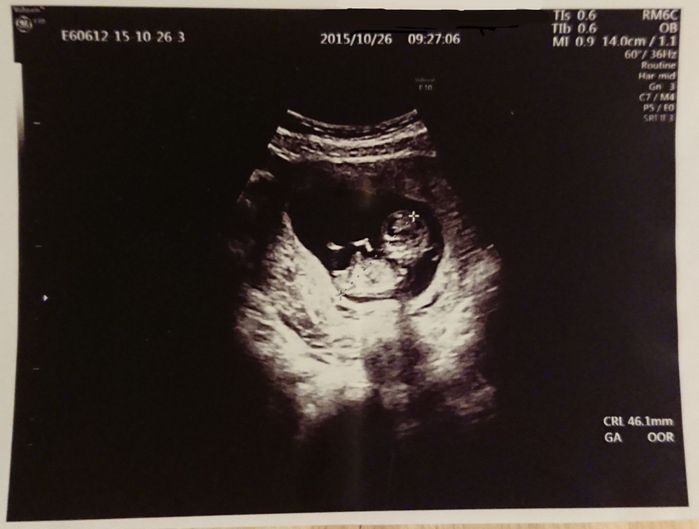

妊娠11週目 1カ月ぶりの健診。エコーを見てびっくり!

頭や手足などがはっきり見えて人間らしくなっていました。この時初めて「かわいい!」と思い、ママになることを実感したように思います。つわりはひどく仕事以外はソファーで横になっている状態。料理も匂いで気持ち悪くなるので作れず、野菜ジュースやゼリーを口にするのが精一杯でした。夫には外食やお弁当などで済ませてもらっていました。